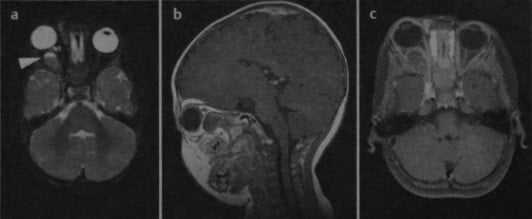

Гемангиома правой глазницы с кровоизлиянием в опухоль (стрелка: уровень жидкости). На Т1 - (а) и Т2-взвешенном изображении (b) визуализируется объемное образование, расположенное внутри конуса, образованного глазодвигательными мышцами. На П-взвешенном изображении (с) после введения гадолиния наблюдается незначительное усиление сигнала от опухоли.